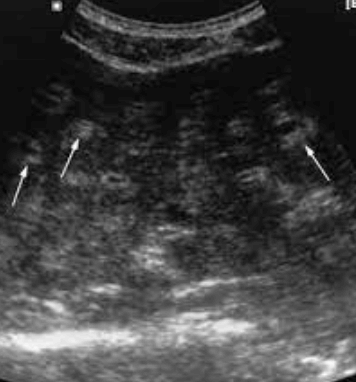

US finding

- 전반적으로 에코가 거칠게 보이는 간경변의 초음파소견과 비슷하여 주의가 필요함.

- 크기가 비슷한 고에코 또는 저에코 병변들이 보인다.

- 다중반사에 의한 comet-tail artifact를 보인다.